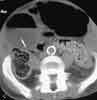

You order a CT scan with contrast to investigate theabnormality. An axial image at the level of the kidneysconfirms the presence of dilated bowel (B, arrow). Thereis no evidence of pneumatosis or bowel-wall thickening.An image at the level of the iliac crests shows a prominentgas-fluid level in the ascending colon, which would correlatewith an obstruction (C, arrow). This image also confirmsthat there are no dilated loops of small bowel. Athird CT image, at the level of the middle pelvis, revealscontrast in the bladder and rectum (D). Careful inspectionshows that the rectosigmoid junction has a "beaked"appearance (arrow).